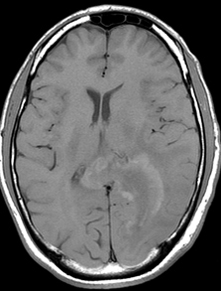

Un défaut de maturité ou de maturation ?

M. Laurent Guilloton HIA Desgenettes - Lyon

Un homme âgé de 33 ans, droitier, sans antécédents médicaux personnels ou familiaux, fut pris en charge, en janvier 2007, devant une symptomatologie visuelle avec la découverte d’une hémianopsie latérale homonyme droite isolée, le reste de l’examen clinique, neurologique et général, étant sans point d’appel.

L’IRM révéla l’existence d’une lésion siégeant au niveau du carrefour gauche. La lésion apparaissait en discret hypersignal T1 avec un réhaussement après injection de gadolinium.

L’IRM montra une expansion de la lésion, laquelle apparaît avec